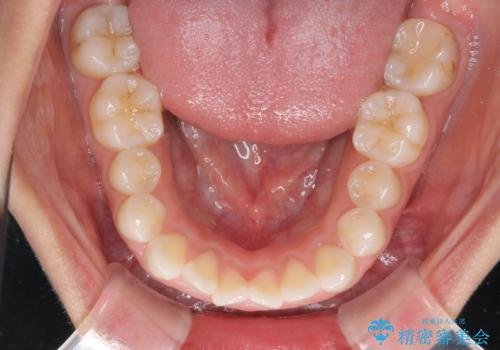

目立たない装置で横顔のシルエットを改善 ハーフリンガルでの抜歯矯正

- 口元の突出感を気にして来院された患者様です。

上下左右の第一小臼歯4本を抜歯して口元を下げる治療計画としました。